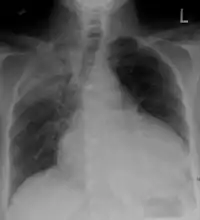

Chest x-ray: is non-specific and may not help identify a pericardial effusion but a very large, chronic effusion can present as "water-bottle sign" on an x-ray, which occurs when the cardiopericardial silhouette is enlarged and assumes the shape of a flask or water bottle.[2] Chest radiograph is also helpful in ruling out pneumothorax, pneumonia, and esophageal rupture.

Pericardial effusion due to malignancy. Note bulbous heart and primary lung cancer in right upper lobe.